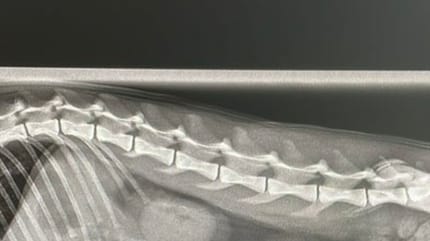

L'équipe de soignants lui a fait passer une radio et c'est là qu'ils ont découvert l'origine de ses troubles gastriques.

Au milieu des organes digestifs se trouvait... une vis intacte. Le chat avait ingéré cette vis sans que son maître ne s'en rende compte.

Le vétérinaire a pu opérer le chat pour retirer la vis au plus vite. Il est heureusement indemne aujourd'hui.